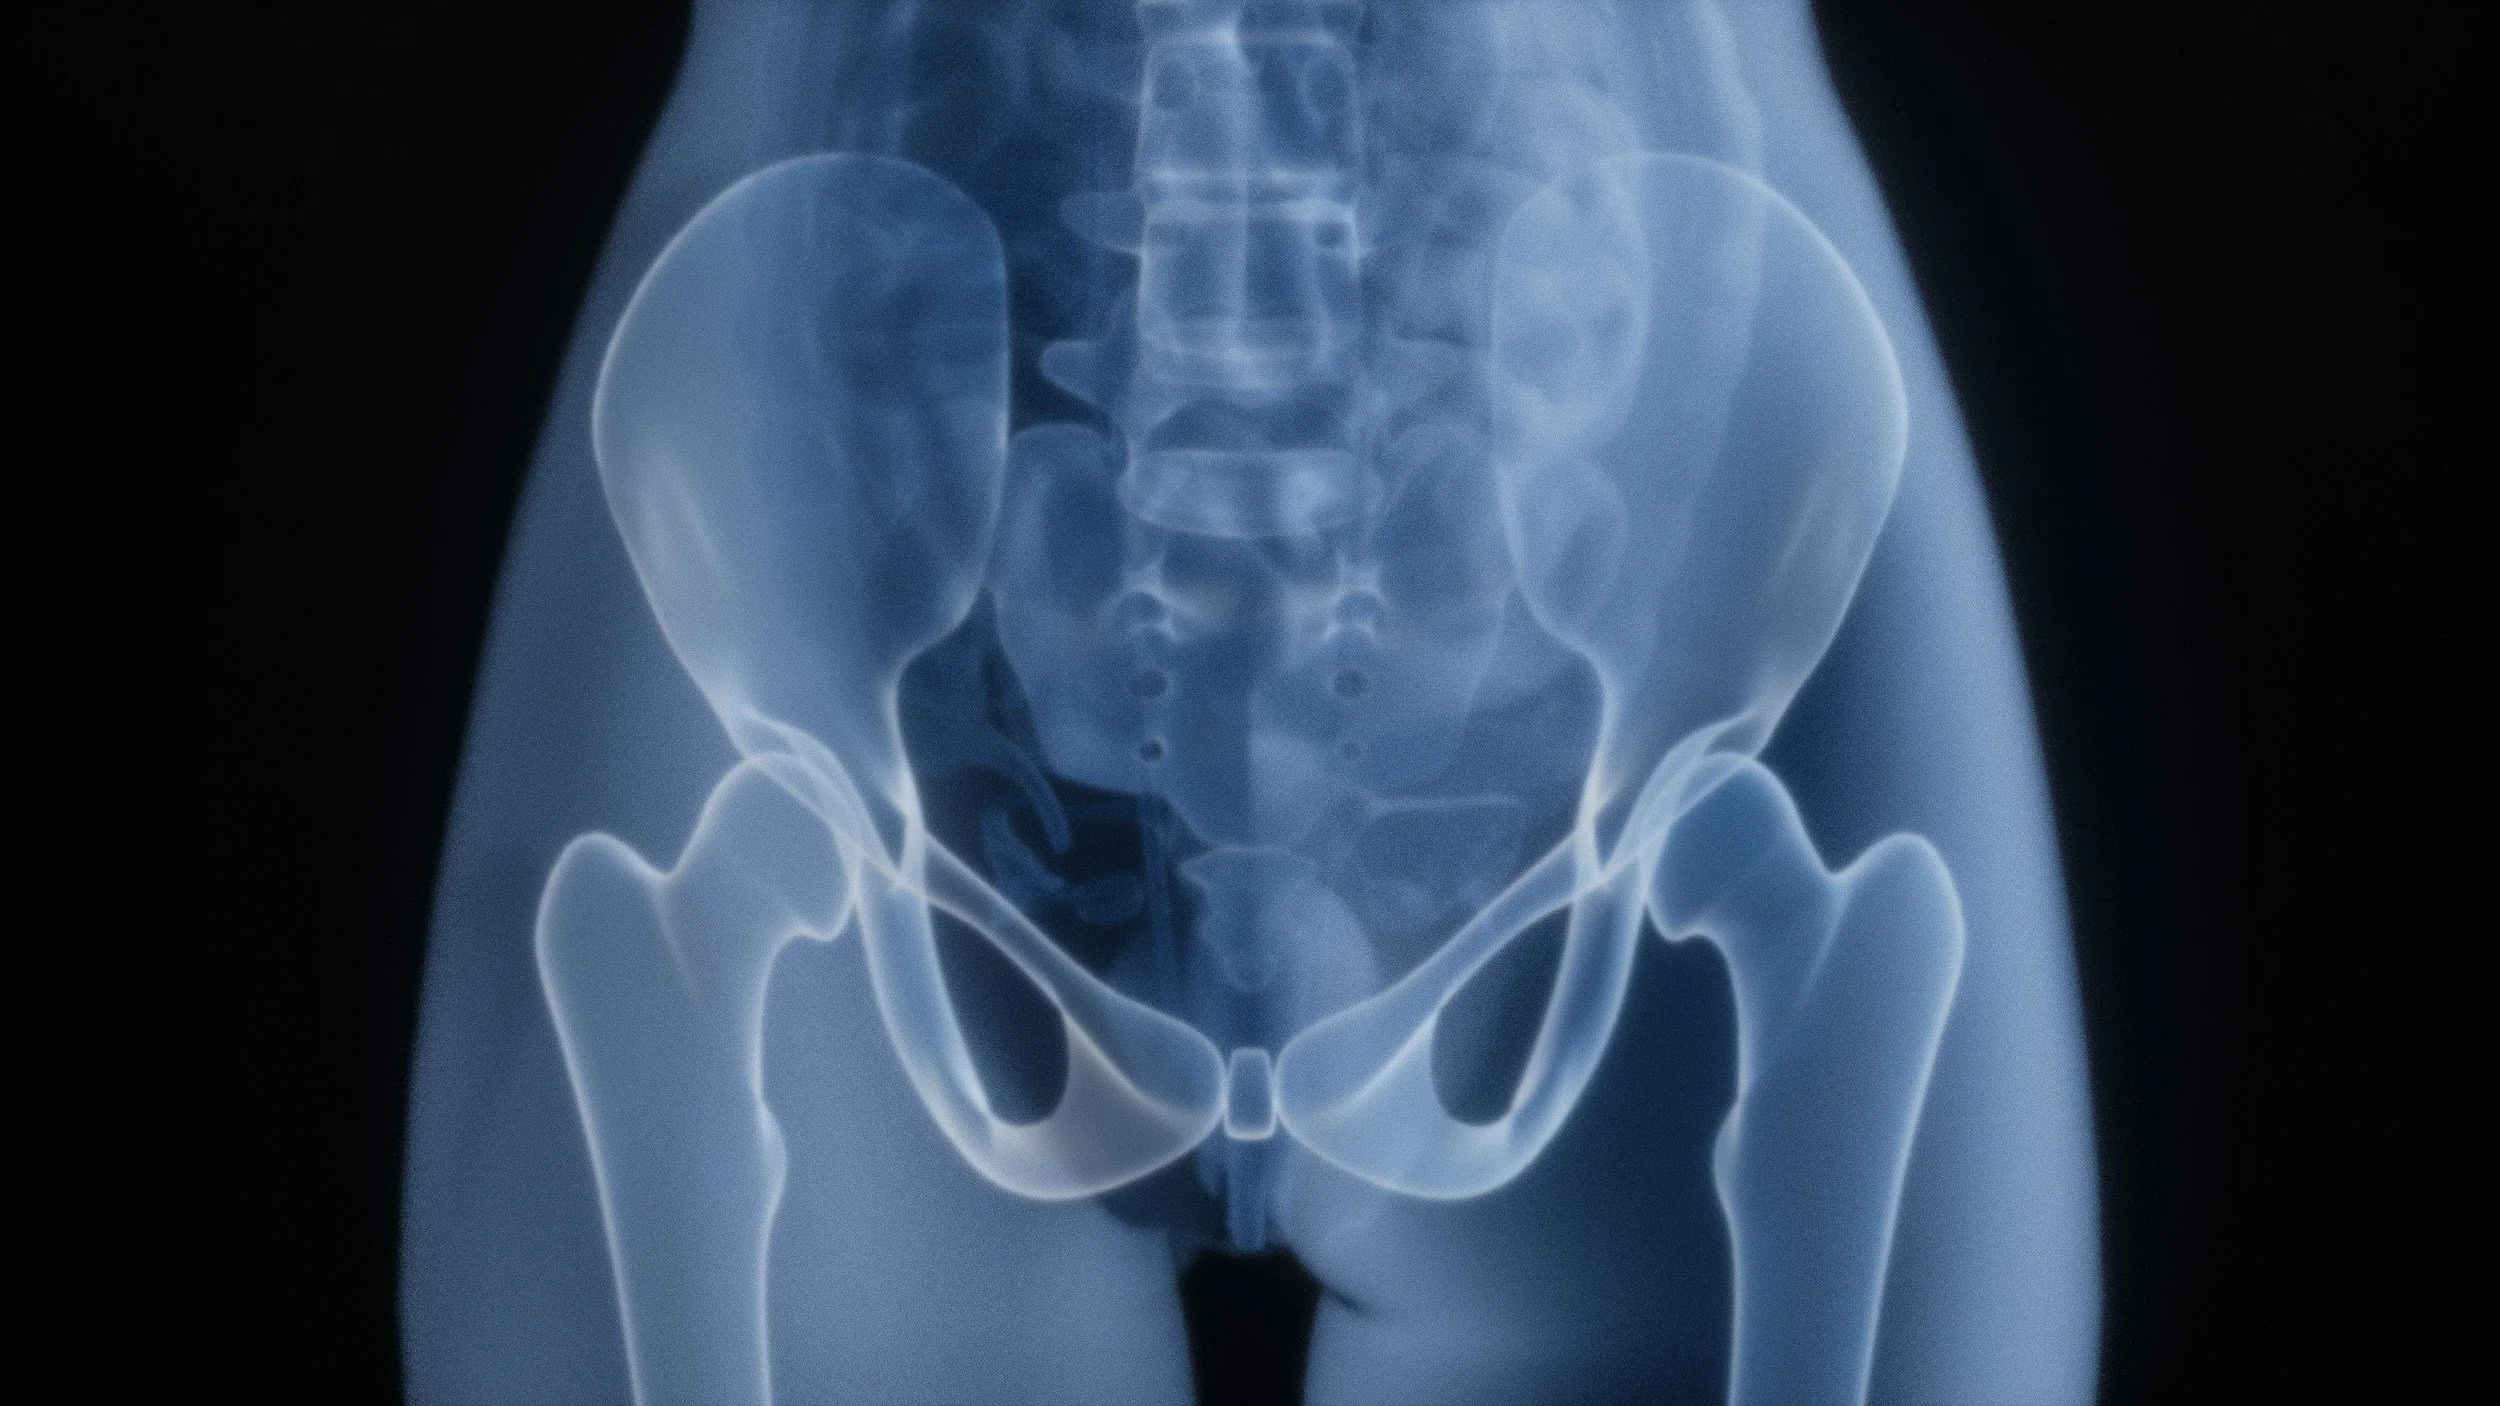

OA can strike any joint, but it’s most common in the hands, knees, hips, lower back, neck, toes and fingers, according to the American College of Rheumatology. Signs that you’re starting to develop a problem include pain during activity, mild morning stiffness that goes away when you’re out of bed and moving, and joints that are swollen or crack or click when you bend them. “Stiffness and swelling are related to inflammation,” says Dr. Cappelli.